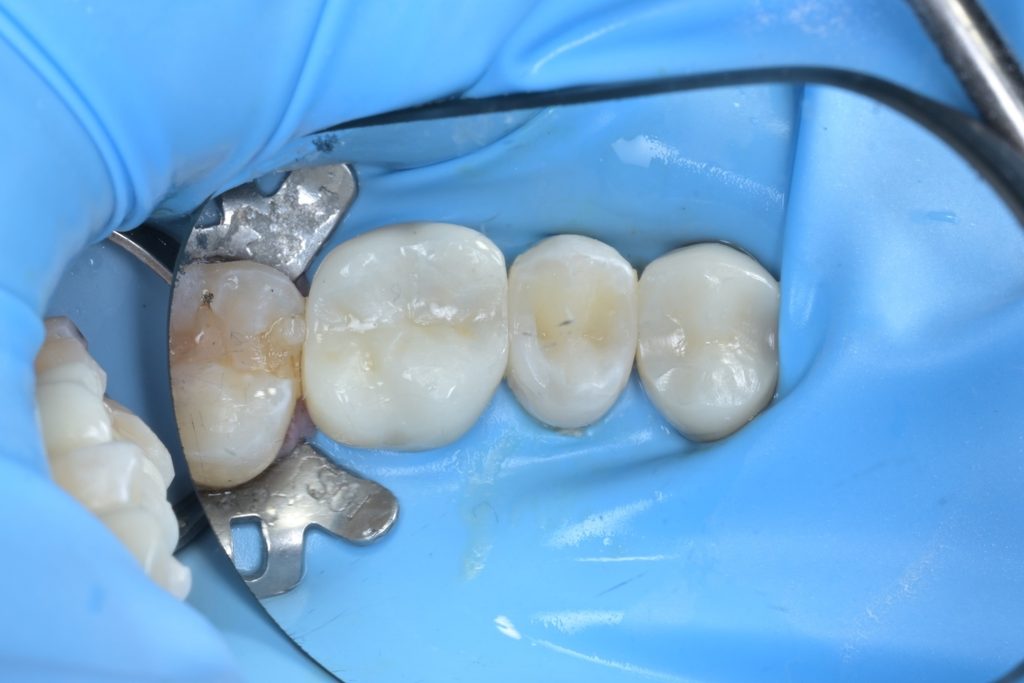

Step 5: 레진빌드업 수복

MTA가 경화되면, 그 위로 복합레진을 이용한 레진빌드업을 시행합니다. 인접면부터 교합면까지 층층이 적층하며 원래 치아의 해부학적 형태를 정밀하게 재현합니다.

치료 후 최종 마무리 및 결과

레진빌드업 완료 후, 교합지를 이용하여 반대편 치아와의 교합 접촉을 세밀하게 조정하고, 다이아몬드 버와 폴리싱 시스템을 사용하여 최종 연마를 진행했습니다.